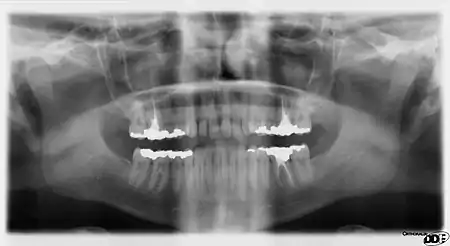

Rarely, a bifid inferior alveolar nerve may be present, in which case a second mandibular foramen, more inferiorly placed, exists and can be detected by noting a doubled mandibular canal on a radiograph.[4]

Fracture

One fifth of facial injuries involve a mandibular fracture.[9] Mandibular fractures are often accompanied by a 'twin fracture' on the opposite side. There is no universally accepted treatment protocol, as there is no consensus on the choice of techniques in a particular anatomical shape of mandibular fracture clinic. A common treatment involves attachment of metal plates to the fracture to assist in healing.[10]

The mandible may be dislocated anteriorly (to the front) and inferiorly (downwards) but very rarely posteriorly (backwards). The articular disk of the temporomandibular joint prevents the mandible from moving posteriorly, making the condylar neck particularly vulnerable to fractures.[5]

The mandibular alveolar process can become resorbed when completely edentulous in the mandibular arch (occasionally noted also in partially edentulous cases). This resorption can occur to such an extent that the mental foramen is virtually on the superior border of the mandible, instead of opening on the anterior surface, changing its relative position. However, the more inferior body of the mandible is not affected and remains thick and rounded. With age and tooth loss, the alveolar process is absorbed so that the mandibular canal becomes nearer the superior border. Sometimes with excessive alveolar process absorption, the mandibular canal disappears entirely and leaves the inferior alveolar nerve without its bony protection, although it is still covered by soft tissue.[4]